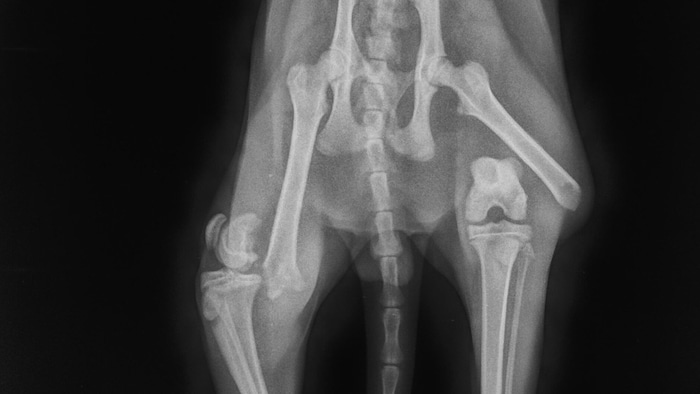

Das Röntgenbild zeigt das Leid, das „Tiger“ nach dem Unfall durchlebt haben muss.

Das Röntgenbild zeigt das Leid, das „Tiger“ nach dem Unfall durchlebt haben muss.(Bild: Tierschutzverein St. Pölten)

Eine schmerzhafte Odyssee muss Kater „Tiger“ in St. Pölten hinter sich haben. Er war angefahren und vor einigen Tagen auf der Straße liegend gefunden worden. In der Tierklinik zeigte sich nicht nur, dass beide Oberschenkel gebrochen waren, die Brüche müssen auch mindestens zehn Tage alt sein.